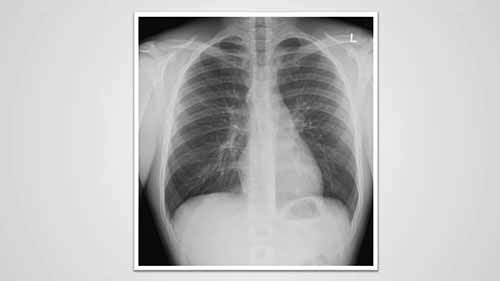

了解胸部X光——形状的重要性

在今天的教学视频中,你将了解气管,主动脉,心脏等组织在胸部X光片上呈现出什么形状。

了解胸部X光——灰度的重要性

不同密度的组织在胸部X光片上呈现出不同的灰色阴影。我们一起来看看空气、软组织、骨头和金属在x光片上是什么样子。